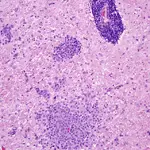

• NME has both a characteristic anatomic distribution pattern and unique histologic lesions:

Gross lesions occur as asymmetrical, multifocal bilateral areas of either acute encephalitis or chronic foci of malacia, necrosis, and collapse of hemispheric gray and white matter decreasing in intensity rostrocaudally.

Histologically, there is a unique combination of focal meningitis and polio- and leukoencephalitis of adjacent white matter. The lesions are intensely inflammatory with meningitis and parenchymal histiocytic, microglial infiltrates accompanied by perivascular cuffing of lymphocytes and plasma cells.

Coexisting with chronic lesions can be acute nonsuppurative encephalitis in the hippocampus, septal nuclei, and thalamus. Usually, few inflammatory lesions are present in the cerebellum, brainstem, and spinal cord (Figure 4).

Figure 4

NME. Intense nonsuppurative meningitis with polioencephalitis and necrotizing leukoencephalitis. The lesions are intensely inflammatory with parenchymal histiocytic, microglial infiltrates accompanied by perivascular cuffing of lymphocytes and plasma cells. (_H&E stain, 110×)._